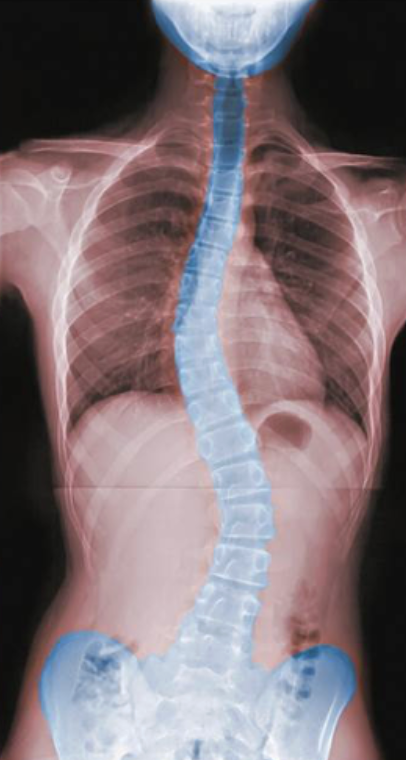

Scoliosis

abnormal lateral curvature